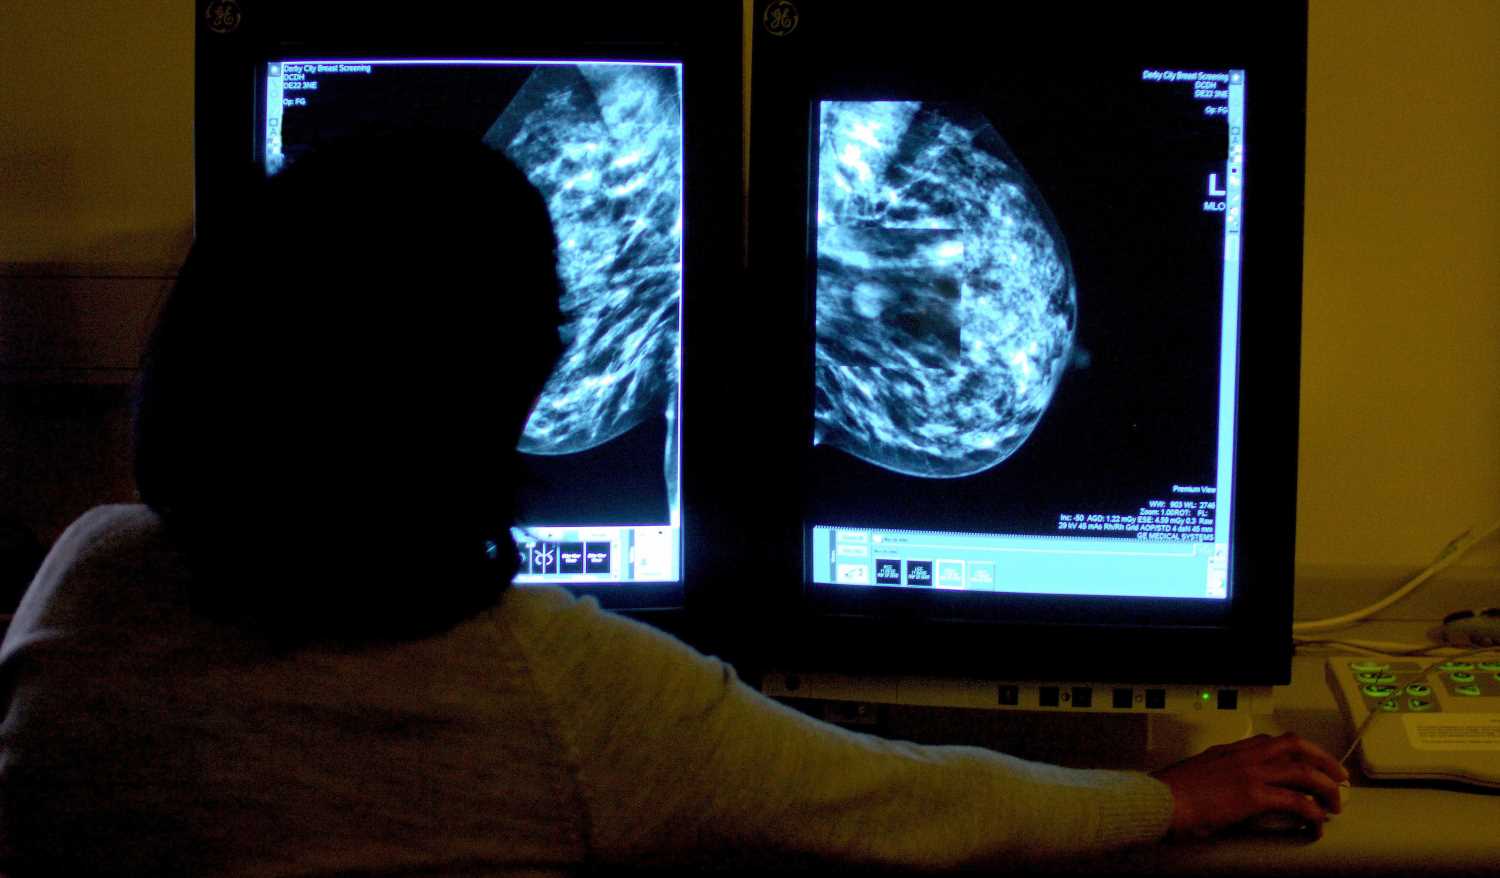

AI could be better at spotting dangerous breast cancer than traditional methods, researchers say.

Computers accurately predicted whether the deadly disease was likely to spread in five years from a mammogram more often.

They were tested against standard clinical models that use information including age and family history as well as mammograms to assess women’s risk.

The AI outperformed the standard model when looking at more than 18,000 women who were screened in 2016 and tracked till 2021 — but researchers aren’t sure how exactly.

Dr Vignesh Arasu, of Kaiser Permanente Northern California, said: “AI is identifying both missed cancers and breast tissue features that help predict future cancer development.

“Something in mammograms allows us to track breast cancer risk.

“This is the ‘black box’ of AI.”

All women aged between 50 to 71 registered with a GP are invited by the NHS for a mammogram every three years as part of a national screening programme.

If the scan reveals no sign of cancer, women are invited back to another one in three years, but clinical models can be used to predict their risk based on their age and family history.

The study, published in Radiology, looked at data from US women who had mammograms in 2016 that showed no visible evidence of cancer.

Of those, 4,584 were diagnosed with the disease within five years of the scan.

Researchers used five AI algorithms to generate cancer risk scores for within a year and from one to five years, as well as within any point over the five years.

All five of the algorithms performed better than the traditional risk model in terms of predicting their likelihood of getting breast cancer.

Dr Arasu said: “Clinical risk models depend on gathering information from different sources, which isn’t always available or collected.

“AI for cancer risk prediction offers us the opportunity to individualise every woman’s care, which isn’t systematically available.

“It’s a tool that could help us provide personalised, precision medicine on a national level.”